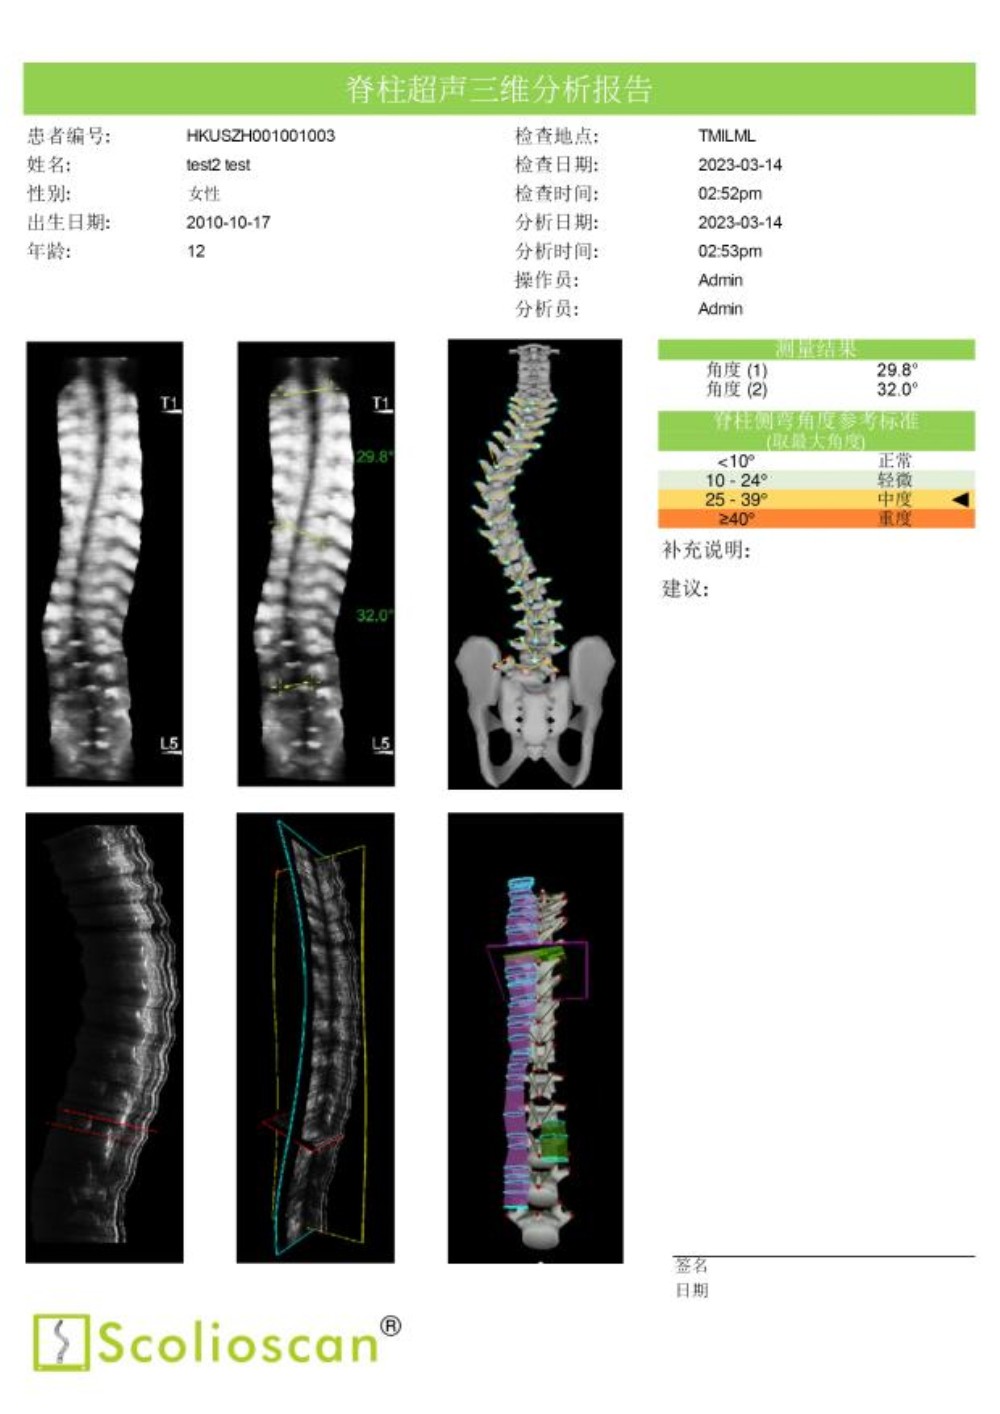

临床试验结果显示,Scolioscan®的测量结果与X光成像高度一致,线性相关度达到0.9464。使用Scolioscan®及早发现青少年的脊柱侧弯问题后,医生得以把握宝贵的黄金治疗时机,通过非手术方式有效控制和治愈疾病,实现早诊断、早治疗、早康复。

通过动态监测侧弯治疗情况,医生能有效帮助孩子选择适合的运动与锻炼方法。密切的超声监测有助于医生在疾病治疗的黄金期积极追踪病情和评估、调整治疗方案,根据脊柱的最新状况,第一时间采用体育运动、手法治疗、支具佩戴等保守疗法为患者矫正,有效减小脊柱侧弯度数。Scolioscan®提供的肌骨三维分析还可以协助医生以关节—肌肉—神经三维度为整体,全面进行脊柱侧弯的综合康复治疗。

内蒙古自治区首台“Scolioscan®无辐射三维超声脊柱侧弯评估系统”成功引入91直播 ,可广泛应用于脊柱侧弯筛查、诊断、病情跟踪和预测以及非手术治疗阶段对治疗结果的可视化反馈和评价等多个领域,为广大儿童青少年提供精准度媲美X光的无辐射、安全的脊柱侧弯评估方案,帮助患有脊柱侧弯的孩子早发现、早干预、早康复,竖起脊梁健康成长。